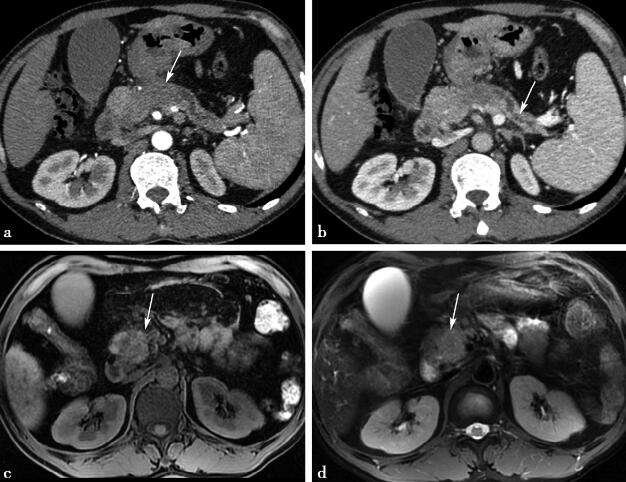

病例4-1-33:CT增强及MRI平扫。

图1a、b,CT增强动脉期和静脉期图像。图1c、d,MRI平扫的LAVA-FLEX和T2-FRFSE图像。胰头区域可见不规则异常密度影(图a箭头所示),动脉期强化程度低于正常胰腺,强化不均匀伴胰体尾区域胰管扩张(图b箭头所示)。MRI中病灶呈长T1稍长T2信号(图c、d箭头所示)